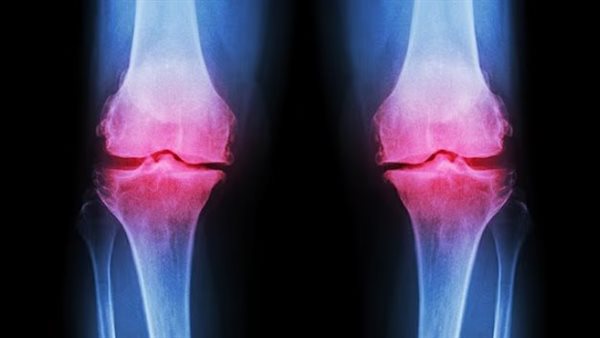

مكمل ألياف بسيط يساعد على تخفيف آلام التهاب المفاصل

أشارت دراسة علمية جديدة أجراها باحثون في جامعة نوتنغهام إلى أن تناول مكمل غذائي منخفض التكلفة من الألياف البريبايوتيكية ويمكن أن يساعد